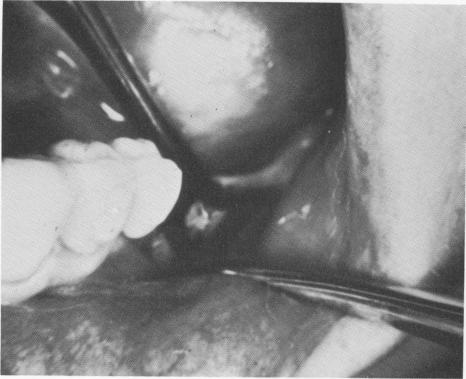

the blade down to its inferior border, and one on the lingual face down to the implant's inferior border (Fig. 4-83).

The bone completely covered the superior surface of both shoulders and had to be removed with a round bur.

Fig. 4-83. Three incisions were necessary to free the firmly affixed blade. (Courtesy R. Buhite.)